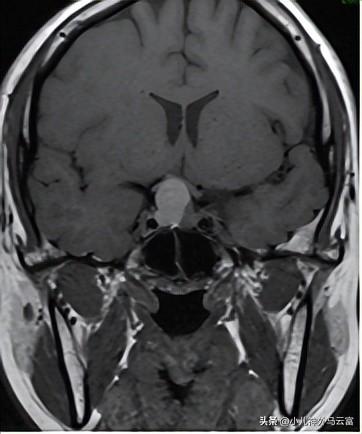

患兒小可,18歲的年紀卻出現了停經甚至泌乳的難言之隱,多地求醫問藥嘗試了中醫、補充激素等多種治療都沒有好的療效,後來湖北省婦幼保健院神經外科,經過檢查,腦部核磁發現鞍區有一個明顯的佔位,激素結果泌乳素明顯增高,醫生團隊結合小可的病史,術前診斷爲垂體瘤。

MRI提示鞍區佔位